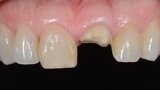

Fig. 22: Fitting assessment of provisional tooth shell.

Fig. 23: Fitting assessment of provisional tooth shell.